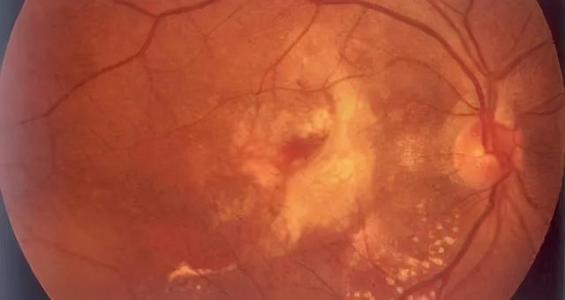

再让我们认识一下黄斑病黄斑疾病的表现视力下降、视物中央暗影、视物扭曲变形、视物变色等是黄斑病患者的常见症状,严重影响着黄斑病患者的生活质量。黄斑病是中老年眼疾致盲的三大元凶之一,在中国城市老年人口疾病发病率呈上升趋势,常见的有老年黄斑变性、视网膜静脉阻塞性黄斑水肿、糖尿病性黄斑水肿、中心性浆液性脉络膜视网膜病变、黄斑前膜、黄斑裂孔等病变。

引起黄斑病变病症越来越多近年来高度近视患者、遗传性眼病变、老年性改变、炎症性病变和其他眼底病变引起的黄斑病变病症也越来越多。为方便黄斑病患者的诊治,南京医科大学附属眼科医院眼底病科特开设黄斑病专病门诊。

多种诊治方式通过与接轨的FFA、ICG、OCT、OCTA、微视野及电生理等的多模式影像技术,定量评估黄斑状态,对各种常见及复杂的黄斑疾病进行诊断,并结合眼内液检测,为后续对针性治疗提供科学的指导依据。

在治疗上,采用多种方法联合治疗模式,除黄斑微创手术、玻璃体腔注射抗VEGF与抗炎药物外,黄斑区微脉冲激光治疗及机器人激光治疗等治疗方式,保护患者视功能,延缓病情发展,为患者制定针对性的治疗方案。